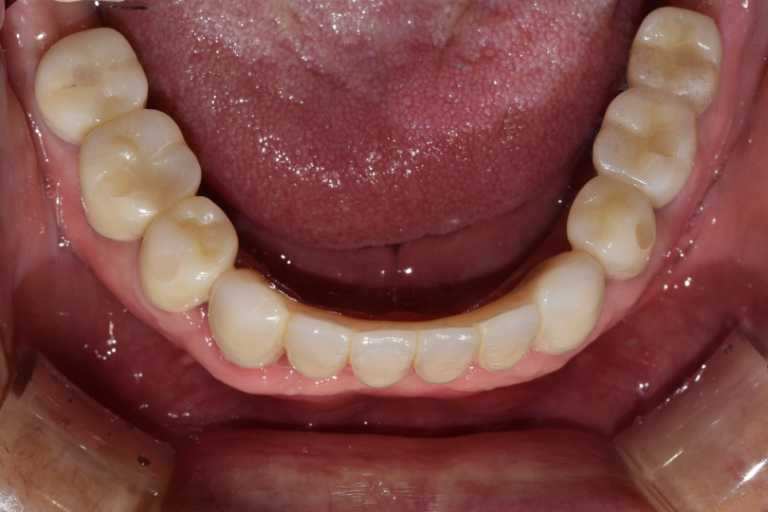

고정형 무치악 임플란트 전후 사례

무치악 임플란트 전후 실제 사례 #1, #2

이미지 위에 가운데 동그라미를 클릭한 상태에서 왼쪽 또는 오른쪽으로 드래그해보세요! 드래그할 때마다 환자의 전후 변화를 확인하실 수 있습니다.

#무치악 임플란트 환자 사례 : 임플란트로 찾은 새로운 미소